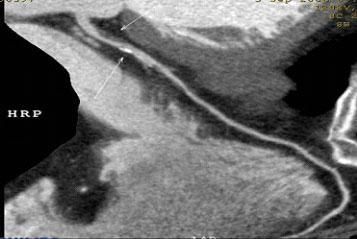

3.對于斑塊性質的确定,CT優于DSA:

二、多層螺旋CT頭頸部及體部血管成像技術:

該機掃描覆蓋範圍廣、時間短,多種後處理分析軟件能顯示各血管細小分支,可以清晰顯示動脈瘤、動脈夾層、血管畸形、血管狹窄及動脈粥樣硬化斑塊等,适用于頭頸部血管成像、肺動脈成像、胸腹部血管成像及四肢血管成像。

1.顱腦血管成像:

動脈瘤

2、頸部血管成像

3、肺動脈血管成像:

4、腎動脈血管成像(腎動脈狹窄):

5、下肢動脈血管成像: